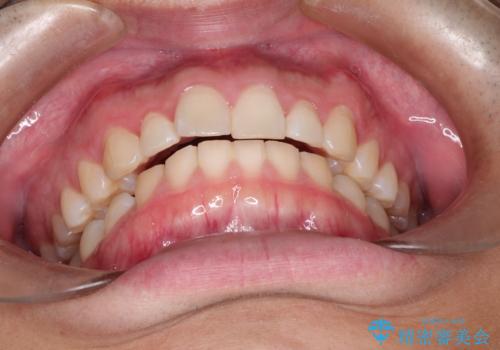

出っ歯が気になる インビザラインによる出っ歯の目立たない矯正

- 出っ歯を主訴に来院されました。

上の歯が全体的に下の歯の位置に比べると前方に位置しており、上の前歯が前方に傾斜している状態でした。

上の奥歯を後方に移動して、隙間を作り、前歯を引っ込める計画としました。